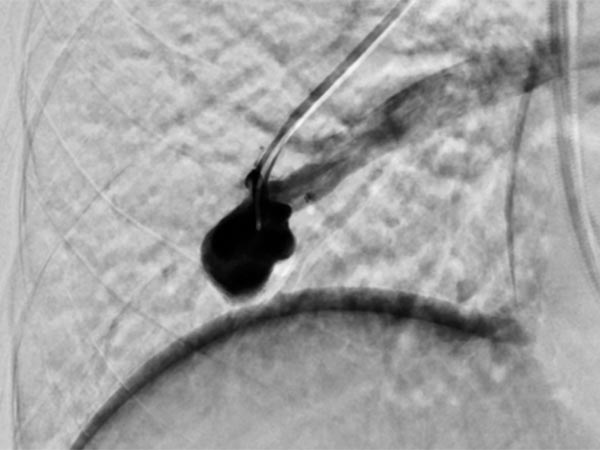

The feeding arteries are occluded with several coils. Parts of the coils are placed in the arterial feeding branch for secure anchoring (anchor technique). The pulmonary AVM is occluded. In the former aneurysm there is still some contrast medium stasis from a previous injection.

Completion DSA via the pulmonary trunk shows no more flow into the pulmonary AVMs.

Completion DSA via the pulmonary trunk in the parenchymal phase confirms complete occlusion of the pulmonary AVMs.